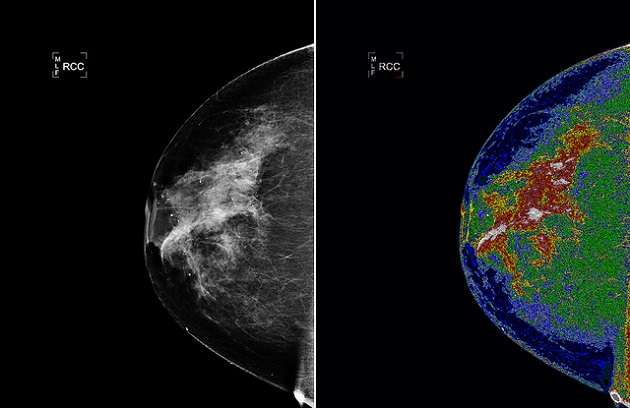

CANCER DU SEIN, LES VRAIS FACTEURS DE RISQUE

Toutes les femmes ne courent pas le même risque de développer un cancer du sein. Or, le dépistage est proposé à toutes après 50 ans, car l’âge […]